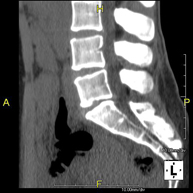

- TC Columna lumbar Prova radiològica que consisteix en obtenir imatges de les vèrtebres lumbars d'alta definició anatòmica, mitjançant l'ús d'un equip de TC (Tomografia Computaritzada). Indicacions: dolor lumbar sense / amb irradiació a les cames, dificultat per caminar, traumatisme. Prova radiològica que consisteix en obtenir imatges de les vèrtebres lumbars d'alta definició anatòmica, mitjançant l'ús d'un equip de TC (Tomografia Computaritzada). Indicacions: dolor lumbar sense / amb irradiació a les cames, dificultat per caminar, traumatisme.

- TC Columna DorsalPrueba radiológica que consiste en obtener imágenes de las vértebras dorsales de alta definición anatómica mediante el empleo de un equipo de TC (Tomografía Computarizada). Indicaciones: dolor dorsal agudo/crónico, traumatismo, columna desviada.